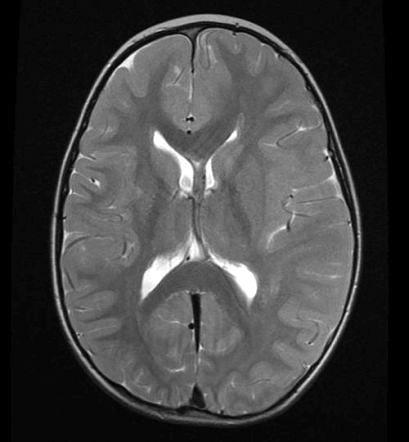

Obrázok vľavo ukazuje, ako asi vyzeral a vyzerá mozog priemerného zdravého človeka od dávnych čias až po súčasnosť, kedy sú obe hemisféry (racionálna aj intuitívna) v rovnováhe a symetrické. Druhý obrázok ukazuje, ako sa asi bude vyvíjať pod obrovským tlakom informácií a konzumácie všetkých tých videí a „zdieľaných“ článkov od množstva kamarátov zo sociálnych sietí. Intuitívna zložka bude výrazne potlačená a rácio v nás hypertrofuje rovnako ako tá jedna hemisféra. Kedysi ľudia aj pri výrazne obmedzených technických možnostiach vnímali prírodu a okolie oveľa intenzívnejšie a osobnejšie. Dnes mladého človeka ani nenapadne večer zdvihnúť hlavu a za jasnej oblohy sa pokochať pohľadom na hviezdy, ako sme to robili my a naši predkovia. Hviezdnu oblohu si dokáže „vygúgliť“ v oveľa väčšom rozlíšení, podobne ako rôzne animácie, prečo by mal byť taký retro… Ortodoxný „mobilmaniak“ už nedokáže ani vystrieť krk, ktorý mu stuhol v predklone, o čom hovorí tretí obrázok.